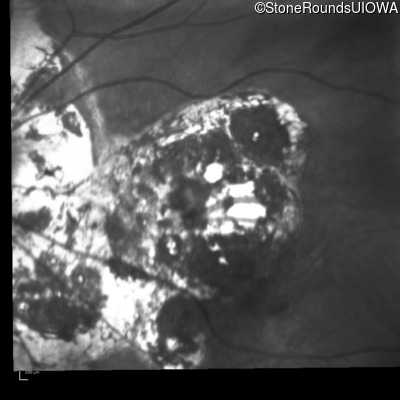

Blue Autofluorescence - Right - 20/160 -2

Exemplar